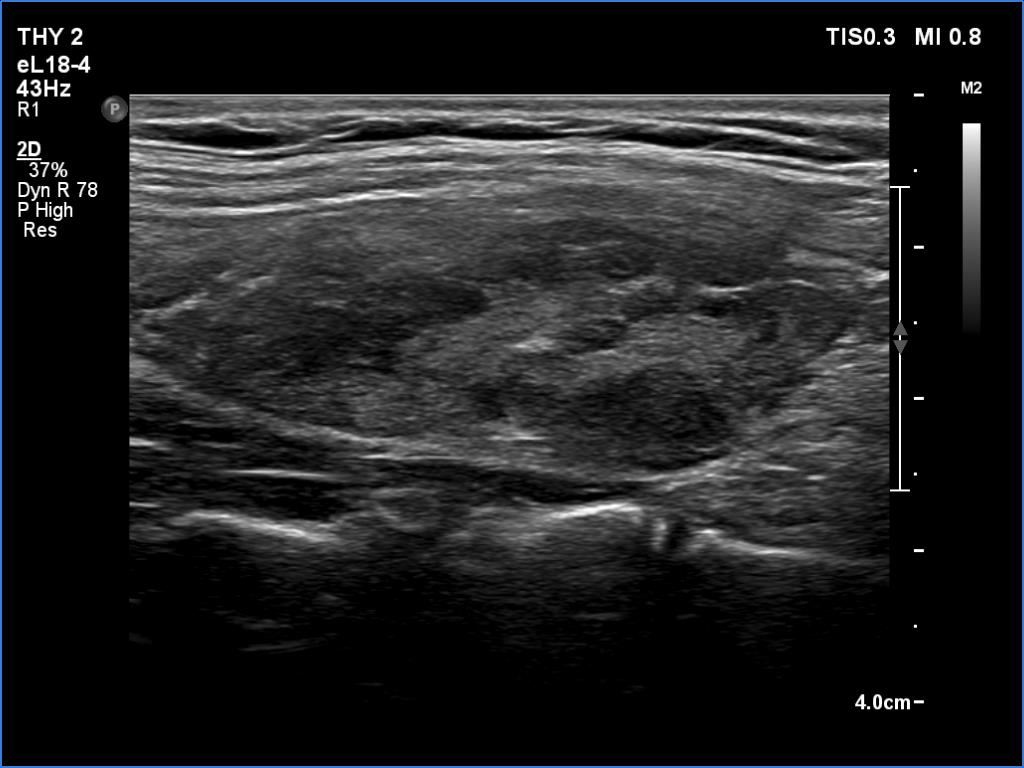

Ultrasonography. The thyroid was echonormal and had hypoechoic areas. The echogenicity index exceeded 50%. The pattern did not correspond to nodule. The vascularity was not specific.

Compared with the previous examinations, the ultrasound pattern remained unchanged.

Comment. This is the most common presentation of Hashimoto's thyroiditis, unfortunately not infrequently misinterpreted as a multinodular goiter. The multiplicity and the irregular borders of the discrete lesions are the main clues to avoid misinterpretation of these lesions as nodules.